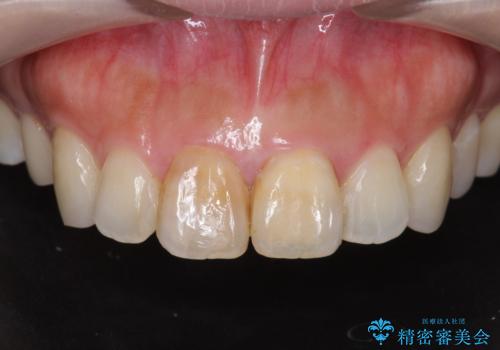

- 歯の神経を除去したのちの、変色の改善を希望され来院されました。

再度根管治療を行ったのちの、オールセラミッククラン治療を計画します。

天然歯を再現したリアルな仕上がりに満足いただくことができました。